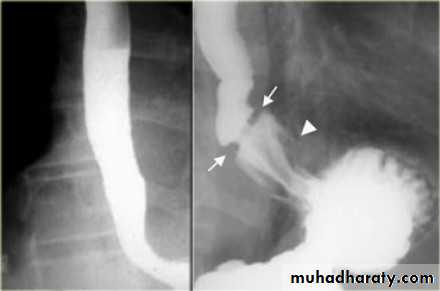

Diverticulum

Types Causes Specific TypeUlcer